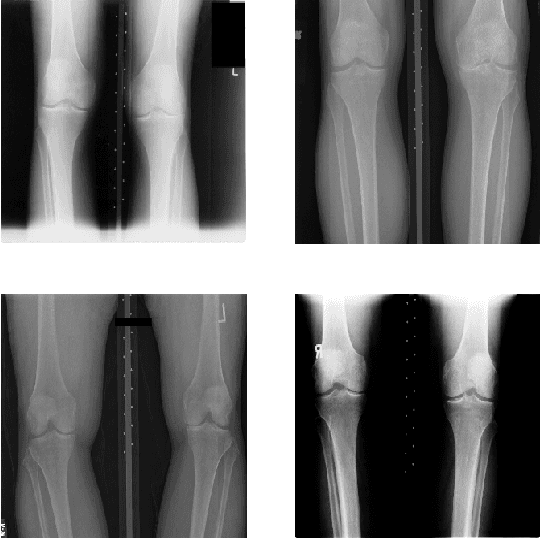

Abstract:This chapter presents the investigations and the results of feature learning using convolutional neural networks to automatically assess knee osteoarthritis (OA) severity and the associated clinical and diagnostic features of knee OA from X-ray images. Also, this chapter demonstrates that feature learning in a supervised manner is more effective than using conventional handcrafted features for automatic detection of knee joints and fine-grained knee OA image classification. In the general machine learning approach to automatically assess knee OA severity, the first step is to localize the region of interest that is to detect and extract the knee joint regions from the radiographs, and the next step is to classify the localized knee joints based on a radiographic classification scheme such as Kellgren and Lawrence grades. First, the existing approaches for detecting (or localizing) the knee joint regions based on handcrafted features are reviewed and outlined. Next, three new approaches are introduced: 1) to automatically detect the knee joint region using a fully convolutional network, 2) to automatically assess the radiographic knee OA using CNNs trained from scratch for classification and regression of knee joint images to predict KL grades in ordinal and continuous scales, and 3) to quantify the knee OA severity optimizing a weighted ratio of two loss functions: categorical cross entropy and mean-squared error using multi-objective convolutional learning and ordinal regression. Two public datasets: the OAI and the MOST are used to evaluate the approaches with promising results that outperform existing approaches. In summary, this work primarily contributes to the field of automated methods for localization (automatic detection) and quantification (image classification) of radiographic knee OA.